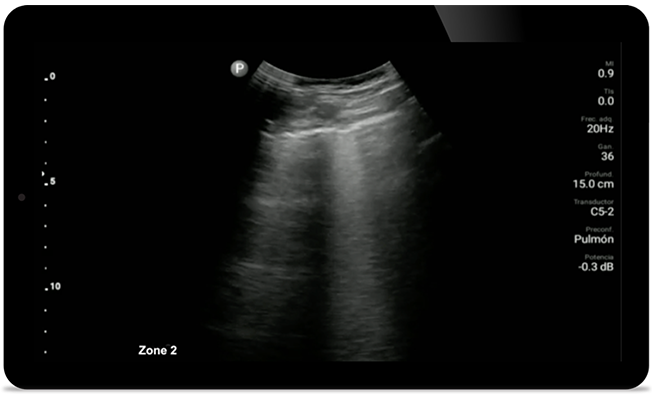

Keep an eye on COVID pneumonia

Lumify can help give results similar to a chest CT when evaluating pneumonia and adult respiratory distress syndrome.